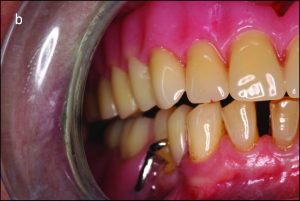

In bilateral balanced occlusion, during lateral movement, there are simultaneous bilateral contacts of opposing posterior teeth on both the working and balancing sides. For example, during a left lateral movement, antagonist tooth contacts occur on the working side primarily through the buccal cusps in the posterior region (Figure 9-4a), while on the opposite side, the buccal cusps of the mandibular teeth are in contact with the palatal cusps of the maxillary teeth. This prevents the right side of the removable prosthesis from lifting off the tissue (Figure 9-4b).

Figure 9-4. In bilateral balanced occlusion during left lateral movement: b) On the non-working side, antagonist contacts occur between the palatal cusps of the maxillary teeth and the buccal cusps of the mandibular teeth.